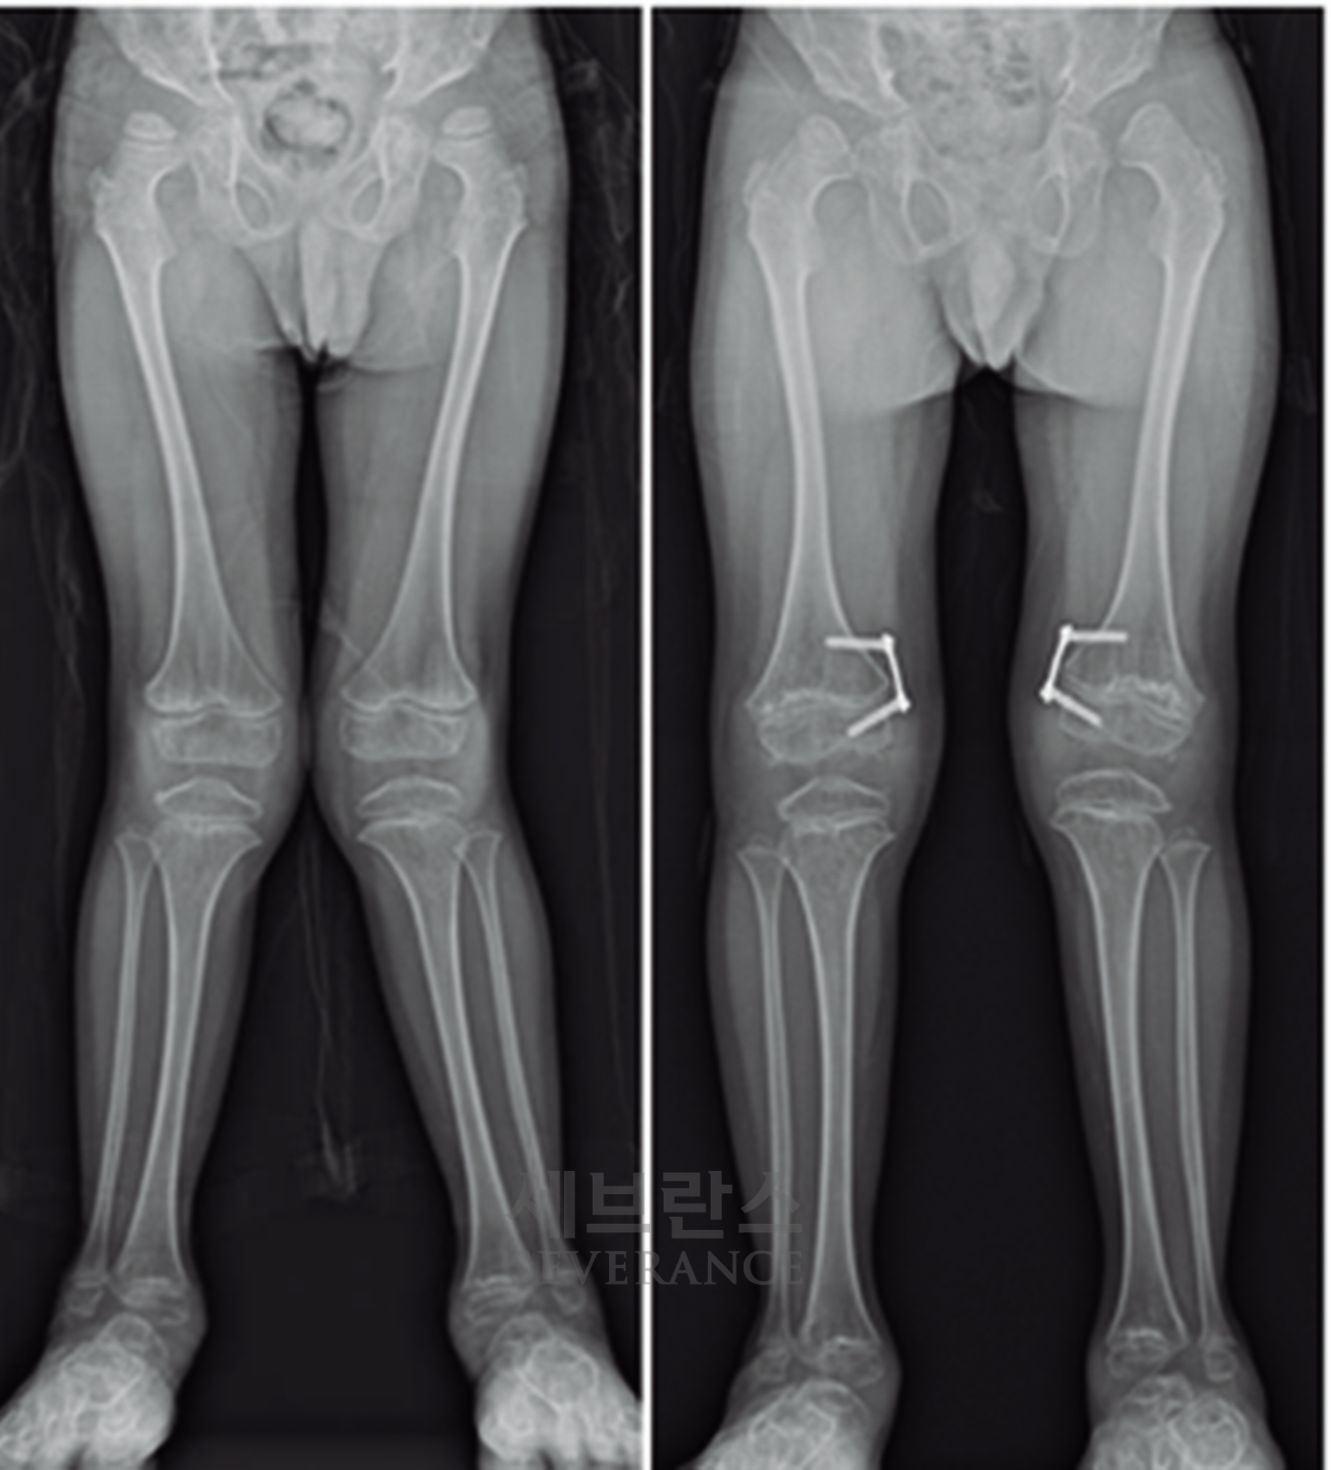

• 절골 교정술

성장이 끝난 환자나 변형이 심한 경우에는 절골 교정술이 효과적입니다. 이 수술은 뼈를 잘라 바른 위치로 되돌린 뒤 금속 장치로 고정하는 방식으로, 수술 직후 곧바로 교정 효과를 볼 수 있습니다. 그러나 절골된 뼈가 단단히 붙을 때까지 약 2-3개월이 소요되며, 그동안은 목발 보행 등 활동에 제약이 따릅니다.

구루병으로 발생한병적 내반슬(O다리) 변형에 대해

절골 교정술을 시행한 환아